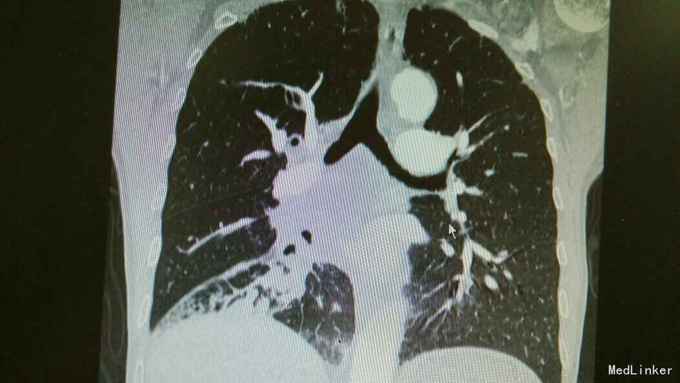

主诉:活动后气促,胸闷1年,消瘦8月余。 病史:患者1年前无明显诱因出现活动后气促,胸闷,主要为胸骨段,爬坡可诱发,伴有咳嗽,白色粘痰。伴有体重下降。

查体:慢性病容,桶状胸,双肺呼吸音粗,右下肺可闻及少量细湿罗音。 辅查:胸部CT:考虑右下肺中央型肺癌并癌性空洞形成,右下肺阻塞性肺炎 ,右下肺动静脉受累,纵隔,双侧肺门多发淋巴结肿大。

诊断:中央型肺癌并阻塞性肺炎。 治疗:入院予以抗感染,止咳化痰等治疗。